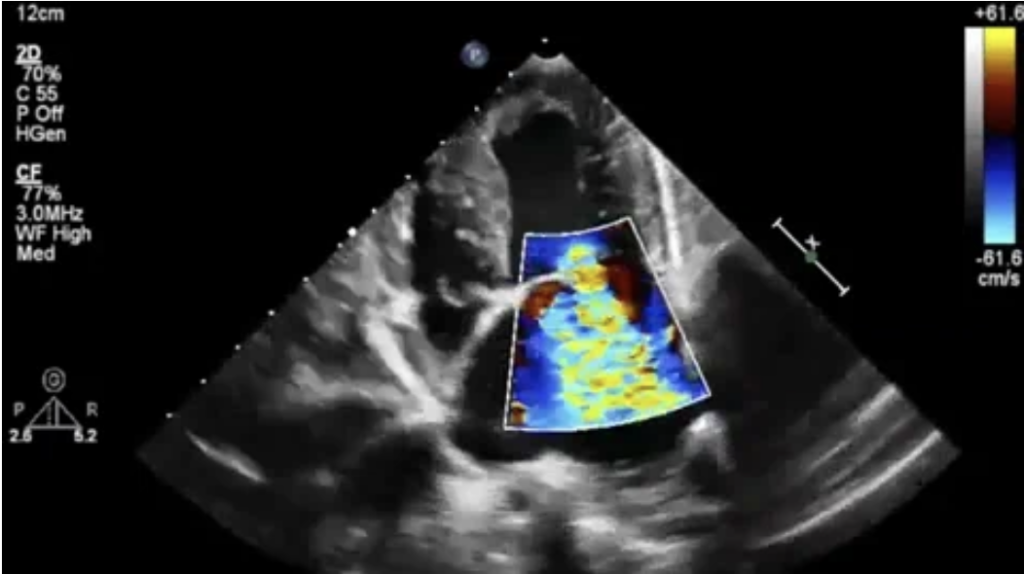

Echocardiography:

Using the art of imaging with ultrasound to view the structure and function of the heart in real time. Ultrasound imaging is incredibly informative, non-invasive, and safe diagnostic in both veterinary and human medical practice. This imaging technique uses high frequency sound waves emitted from a handheld transducer (probe) to produce an ultrasound beam. The beam is reflected off the tissues in the chest and heart back to the transducer to create an image of the heart in motion. Several types of echocardiography are used to show the structure of the heart walls, chambers, and valves (2- or 3-dimensional echocardiography), blood flow direction and velocity (Doppler echocardiography, including color, pulsed and continuous wave) and heart wall motion velocity (Tissue Doppler echocardiography).

·        An echocardiogram helps assess the cardiac function and diagnose many heart conditions. It can also help examine blood flow, assess the quality of blood flow through arteries, and function of the heart valves.